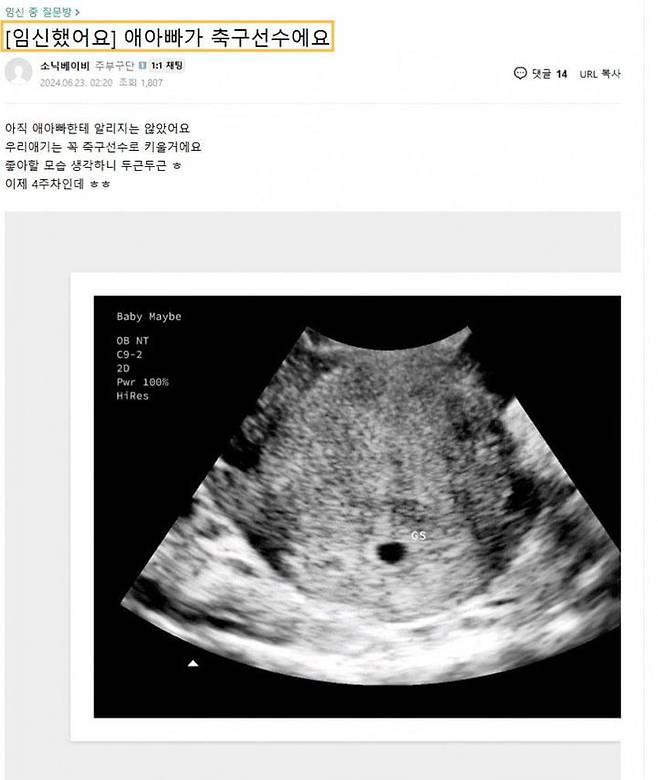

한 네티즌이 올린 초음파 사진도 주목받고 있다. 지난해 6월 '소닉베이비'라는 닉네임을 가진 네티즌이 '아이 아빠가 축구선수'라는 제목으로 한 커뮤니티에 게재한 초음파 사진에는 "아직 아이 아빠에게는 알리지 않았다"며 "우리 아기는 꼭 축구선수로 키우겠다"는 설명이 덧붙여져 있다. 소닉베이비라는 닉네임을 사용한 인물이 양씨라는 주장은 검증되지 않았다.

양씨는 모델업계 종사자로 손흥민과 연인 관계였던 것으로 알려졌다. 지난해 6월 "임신을 했다"며 초음파 사진을 보냈고, 이후 "임신을 외부에 알리지 않겠다"는 취지의 각서를 쓰고 약 3억원을 수령한 것으로 알려졌다.